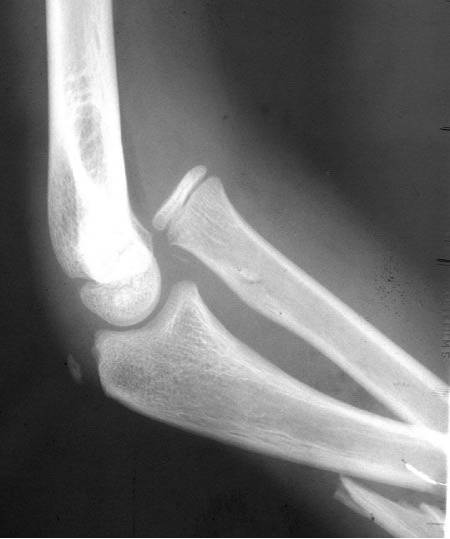

Monteggia骨折

孟氏骨折:桡骨头脱位合并尺骨骨折。